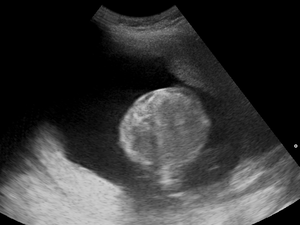

Polyhydramnios (polyhydramnion, hydramnios, polyhydramnios) is a medical condition describing an excess of amniotic fluid in the amniotic sac. It is seen in about 1% of pregnancies.[1][2][3] It is typically diagnosed when the amniotic fluid index (AFI) is greater than 24 cm.[4][5] There are two clinical varieties of polyhydramnios: